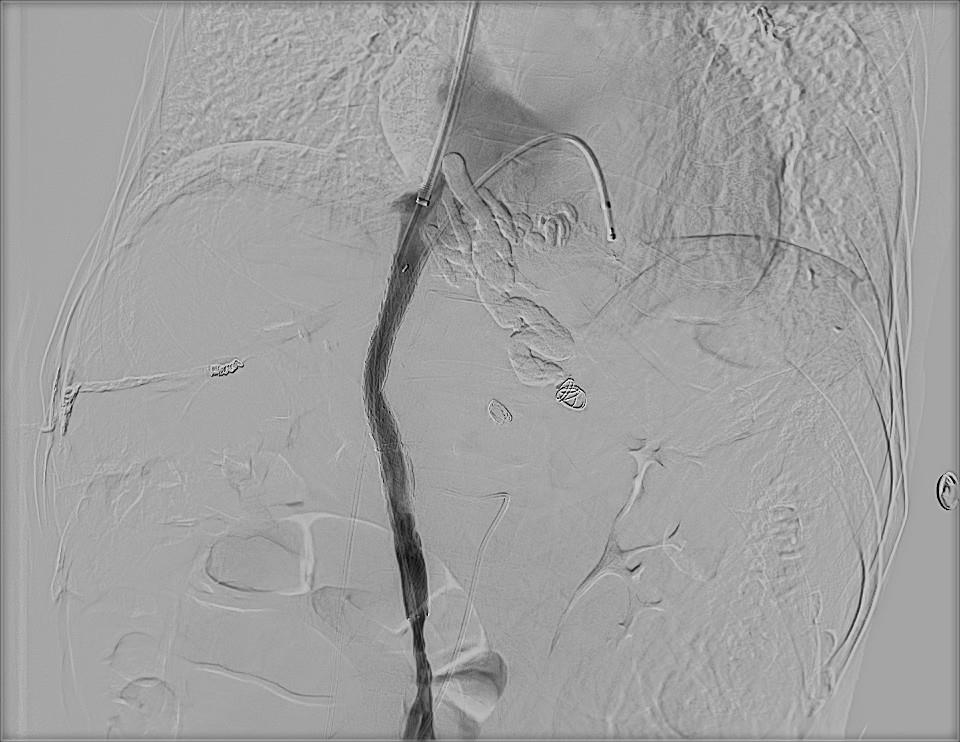

这场高难度DIPS手术,结束了患者长年出血隐患时间:2024-08-01 浏览量:2295 来源: 作者:近日,市四医院消化内科和介入室在原有常规开展的TIPS(经颈静脉肝内门体分流术)基础上,成功开展市内首例门静脉海绵样变的DIPS术(门静脉-腔静脉直接分流术),为患者解决了多年的出血隐患。该项手术的顺利开展,标志着市四医院消化内科和介入室在高难度肝硬化并发症患者的救治上再下一城。 ![]() ![]()

患者受困十余年 四院团队展身手 ![]() 卓先生黑便反复已有十余年,早期未接受正规诊治,于4年前被明确诊断为乙肝后肝硬化伴食管静脉曲张。确诊后,卓先生做了输血、止血治疗,先后接受了内镜下食管静脉曲张套扎止血及行脾脏切除术,症状得到了很大缓解。 然而,卓先生近日再次出现黑便,伴有呕血,遂到市四医院消化内科就诊并做检查。胃镜见:重度食管胃底静脉曲张伴门脉高压性胃病,食管壁上数条蓝色曲张静脉,最粗的地方直径已经有两公分,胃底贲门附近见数条曲张静脉,粘膜多发糜烂、充血灶。CT见:肝硬化,门静脉主干完全闭塞,门静脉分支部分栓塞,门静脉海绵样变,重度食管胃底静脉曲张。 检查结果可见,卓先生的情况不容乐观,且伴有粗大曲张静脉(达2.0cm),而肝移植的治疗方案又超出了卓先生能承受的范围。消化内科与介入团队开展讨论,认为卓先生内镜下治疗困难,且反复出血甚至致死性大出血风险极高,需行分流术降低门静脉压力,降低再出血几率。但是卓先生门静脉主干全程闭塞,且可能闭塞时间较长,开通闭塞的门静脉难度大,要经门静脉主干去建立分流道,是手术最大的困难,也是术中大出血死亡最大的风险点。 ![]() ![]() ![]() ![]() 在与患方充分沟通并取得同意后,消化内科与介入团队决定迎难而上,做足术前准备,为患者安排手术。手术由介入室副主任、副主任医师黄勇及主治医师荣鹏操“刀”完成,在患者完全清醒的状态下,成功开通全程闭塞的门静脉主干,并行门静脉-腔静脉分流(DIPS)及曲张静脉栓塞术,复测门静脉压力梯度达标。术后患者恢复良好。

积极应对困难 顺利通过考验 ![]() 据黄勇介绍,门静脉高压症是肝硬化主要并发症,而食管胃静脉曲张破裂出血是肝硬化门静脉高压的严重并发症,反复出血致死风险高,是内、外科均感棘手的难题。 虽然除肝移植外,介入的TIPS技术(经颈静脉肝内门体分流术)能有效降低门静脉高压,显著降低再出血风险,也可为患者赢得肝移植的机会。但是肝硬化患者凝血功能紊乱,存在“低凝与高凝”并存,一旦门静脉血栓形成(尤其是行脾脏解除术的患者),甚至出现门静脉闭塞、门静脉海绵样变后,门静脉压力将变得更高,出血(甚至腹水)的风险也将更大,这将明显加大手术难度,增加术中门静脉破裂大出血的死亡风险。“但是我们消化介入团队凭借丰富的手术经验,顺利完成了手术,这也体现了团队的硬实力。” 市四医院消化内科与介入团队在门静脉高压所致出血、腹水、门静脉急/慢性血栓、门静脉海绵样变等肝硬化并发症的治疗上积累了丰富的经验,并在提升治疗水平的道路上持续前行,随时准备为盐都人民的健康保驾护航。